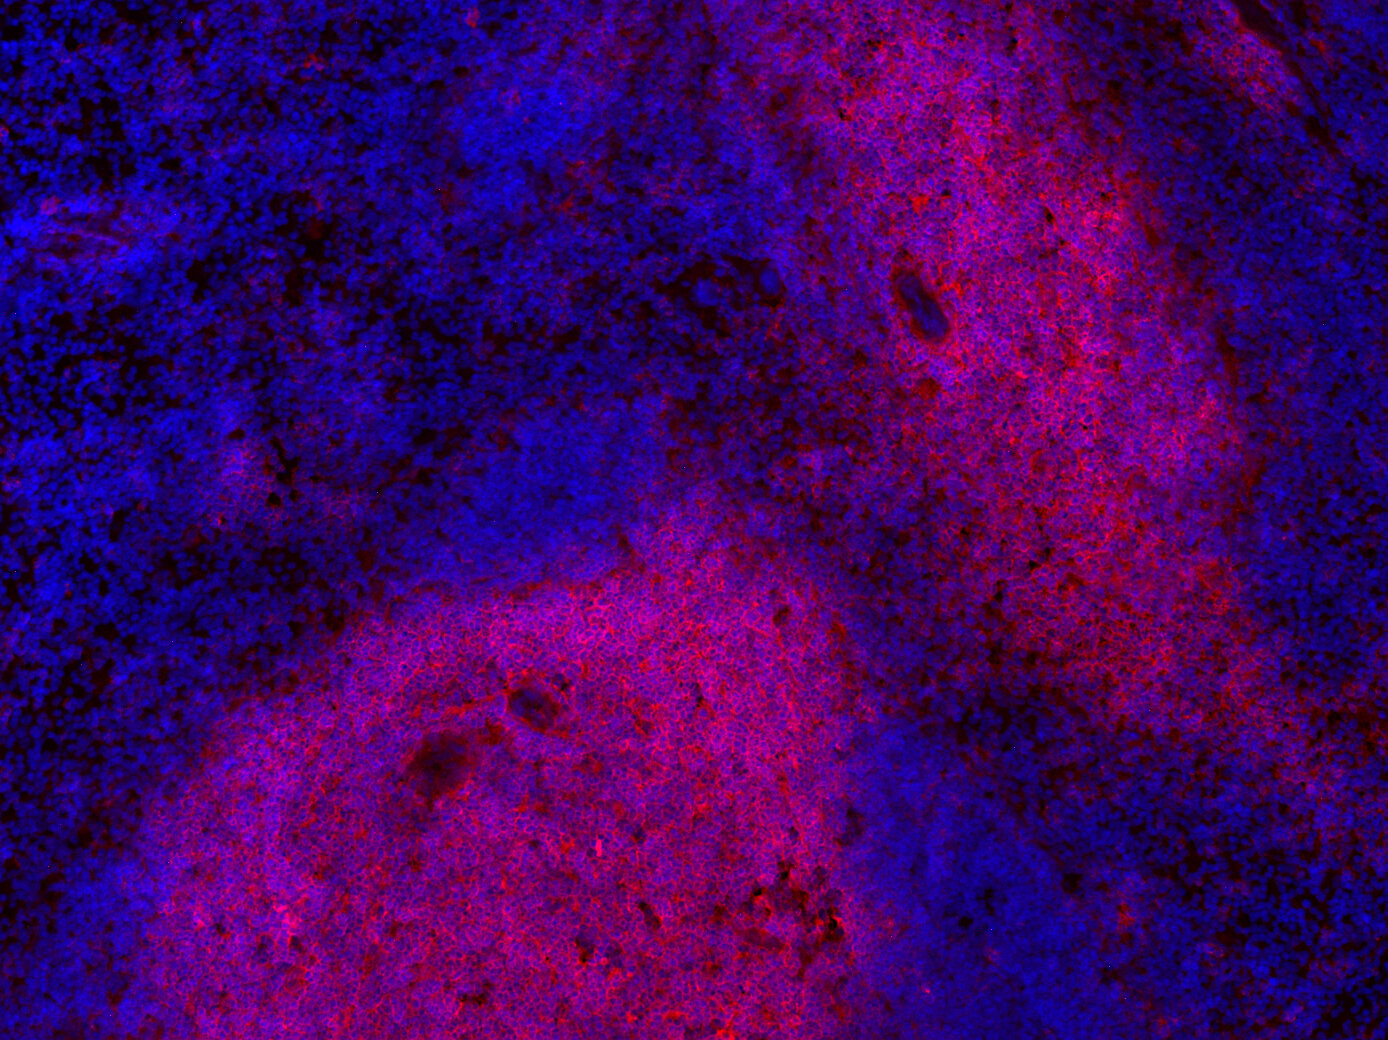

Indirect immunostaining of formalin-fixed paraffin-embedded mouse spleen section with monoclonal rat anti-CD4 (cat. no.: HS-360 117; red) and rabbit polyclonal anti-CD3e (cat. no.: HS-413 103; green) demonstrating the co-localization in CD4 + T-cells (overlay: yellow). Nuclei have been visualized by DAPI staining (blue).